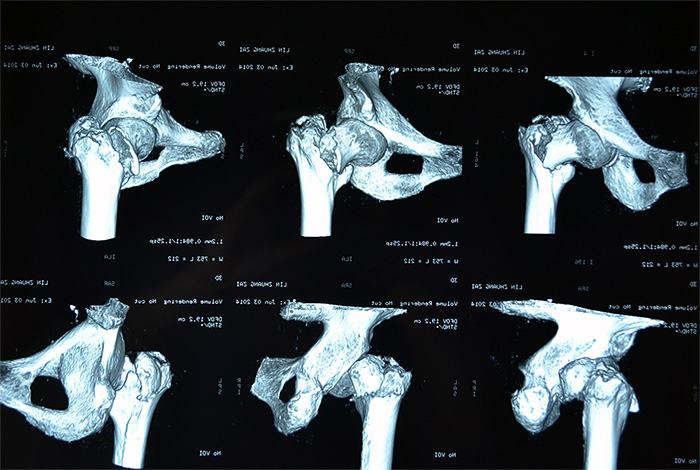

林老太入三院时,左腿的髋部骨折处已翻转90度,还出现短缩移位,左腿比右腿短了5—6公分。由于疼痛,每次大小便,对老人来说都是一次折磨,她也不敢正常摄入食物,导致出现低蛋白,且原先就有高血压的症状,心血管功能比较差,手术风险极高,如果采用传统的骨折开放复位钢板固定术,对于高龄特别是骨质疏松患者,手术失败率很高,同时卧床时间长达三四个月,极易引发并发症。骨科主任刘忠国说。

骨科、心内科、麻醉科等多科专家组成的专家组认真仔细分析病情,决定采用髋关节微创植入内固定术。6月4日,老人接受手术,在手术牵引床上,通过C臂X光机透视,不切开骨折端闭合牵引复位,在老人骨折处复位到最佳状态时,刘忠国在骨折处开出5公分的口进行螺旋刀片动力髋固定,最大程度减少手术损伤,促进骨折端提早愈合。